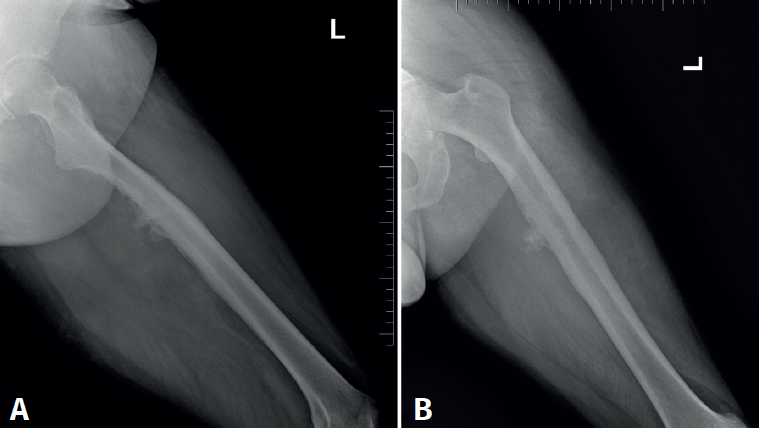

Cincuenta días tras el accidente se realizó fusión lumbar instrumentada L4-L5 con inserción de dispositivo intersomático por vía transforaminal derecha. En el segundo día postoperatorio presentó empeoramiento del dolor, objetivándose en la tomografía computarizada (Figura 2) malposición del tornillo L5 izquierdo que invadía el canal. Se reintervino a los 5 días corrigiendo el trayecto del tornillo. Sin embargo, persistió el dolor. La revaluación del caso, sumada a los hallazgos de EMG, motivó estudios complementarios de pierna y trayecto ciático (Figuras 3 y 4), detectándose una masa tumoral en el fémur izquierdo compatible con sarcoma fusocelular.

Figura 3. Radiografías del fémur izquierdo. A: proyección anteroposterior, con lesión ósea permeativa en la diáfisis femoral con reacción perióstica; B: proyección lateral, con irregularidad cortical y masa de las partes blandas adyacente, sugestiva de lesión tumoral.